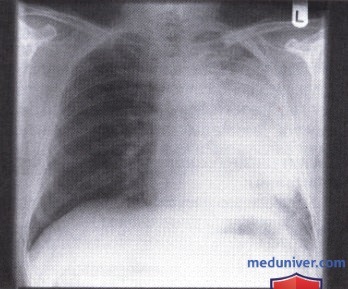

Острая внебольничная пневмония по МКБ-10: признаки и примеры